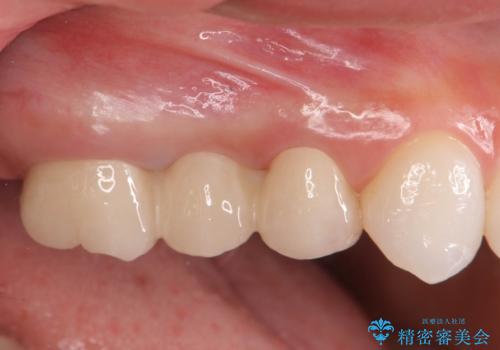

割れてしまった奥歯 セラミックブリッジ治療

ジルコニアブリッジは、インプラントと違い手術の必要がなく審美的に咬合機能の回復ができる補綴手段です。